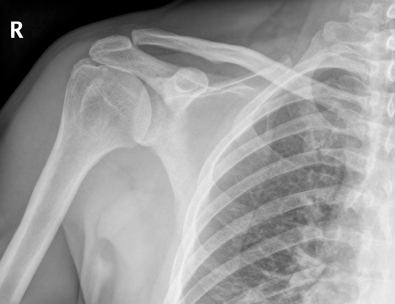

Деформация или разрыв связки между ключицей и плечом. Тяжесть травмы оценивается классом от1 до 6, где травма 6го класса происходит с участием наиболее сильных повреждений связок и окружающих структур. Самым распространенным способом получением травмы является подаение плечо, локоть или на вытянутую руку.

ДИАГНОСТИКА

Изучение истории болезни и медицинский осмотр будет проведены. Диагноз ставится после проведения рентгена и МРТ.

Медицинские процедуры, проводимые при заболевании разрыв акромиально-ключичного сочленения: Спиральная компьютерная томография, Магнитно-резонансная томография, РентгенПРОГНОЗ И ОСЛОЖНЕНИЯ